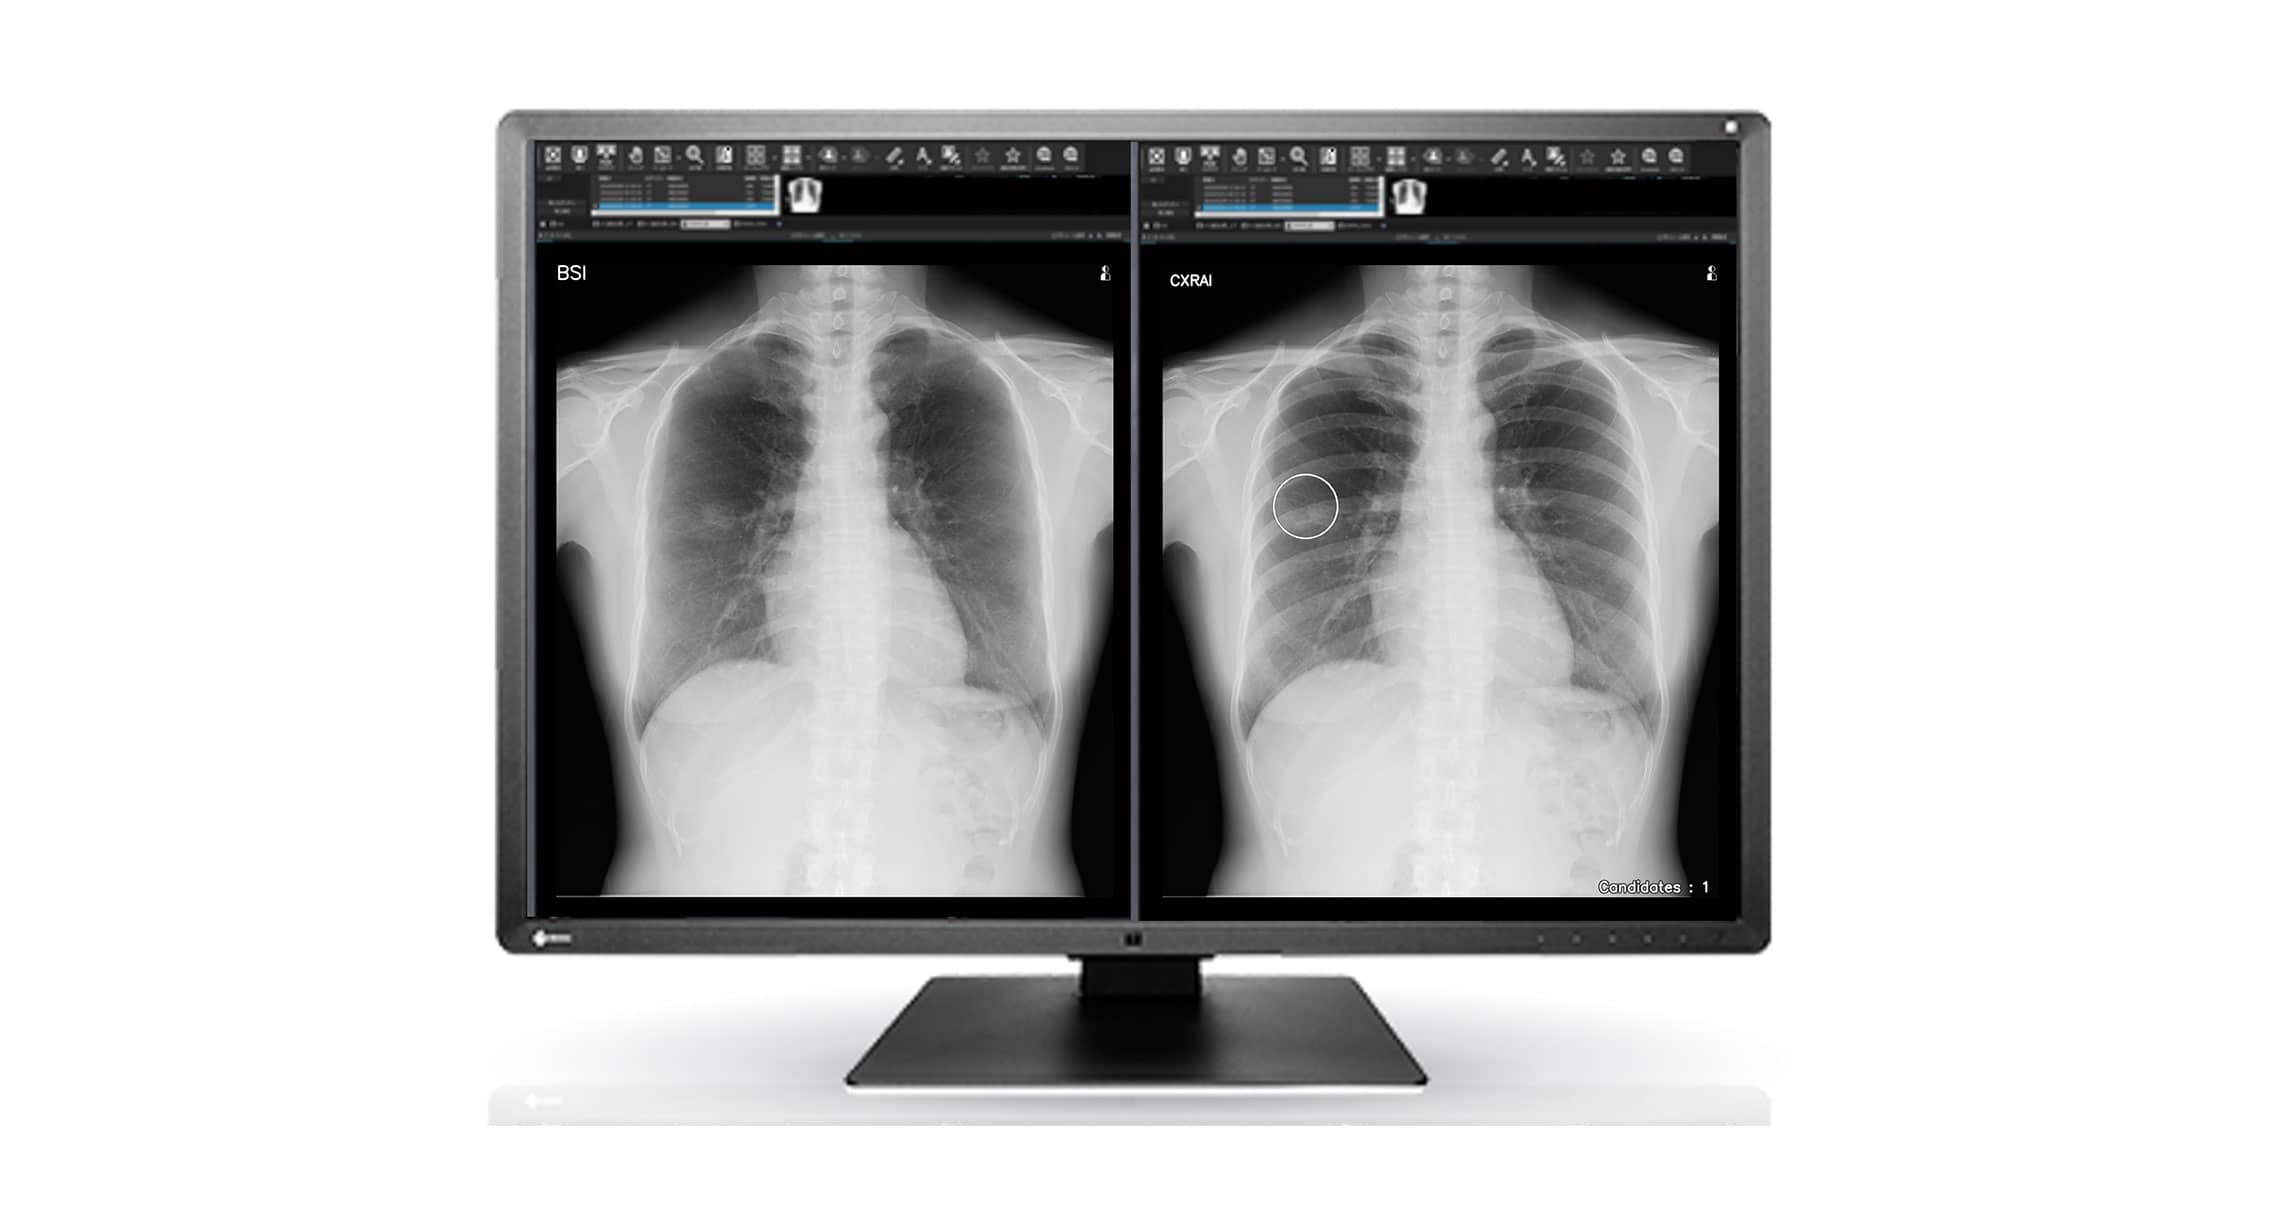

レンズ,シグマ | 三宝カメラ SANPOUCAMERA ONLINE, Senciafinder(センシアファインダー) - ヘルスケア | コニカ,